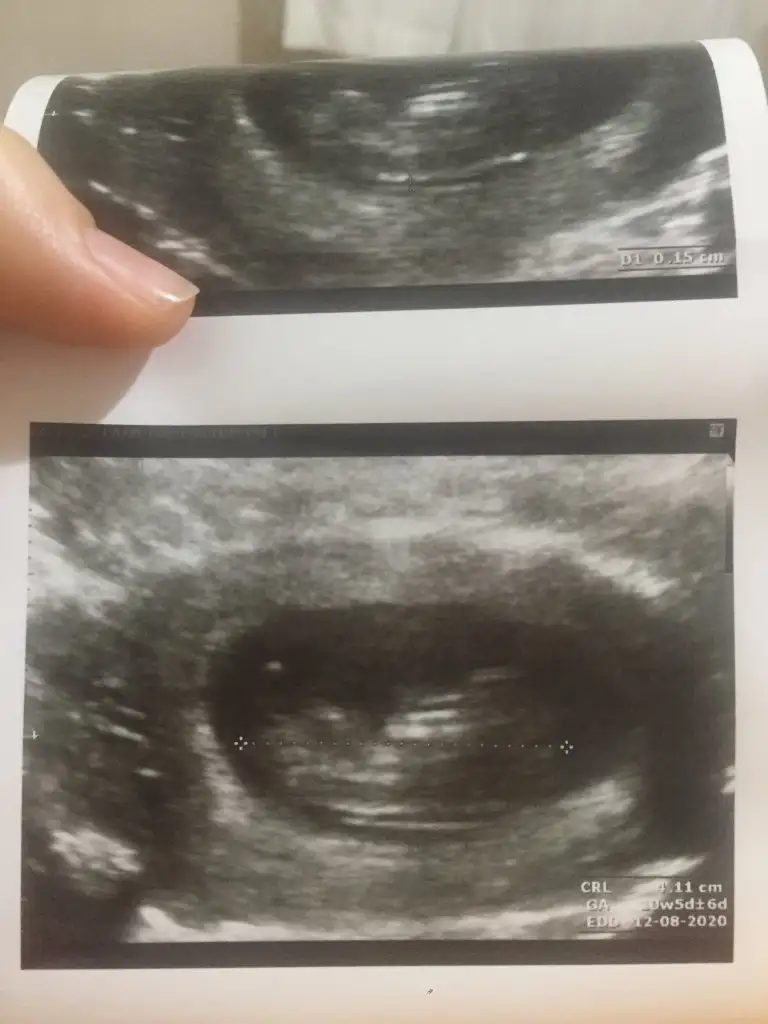

Haftam yaklaştıkça bir merak sardı.

O gözüken nub mu emin olamadım ama yine de bir atayım belki fikir yürüten olur didimm.

10+5 günlük bir kurbağa 🐸 🐣

Ne dersiniz?? Ikra meyra Ikra meyra

Net degil usg 11+ yada 12+ oldugunda paylaşın yada net varsa usg paylaşın